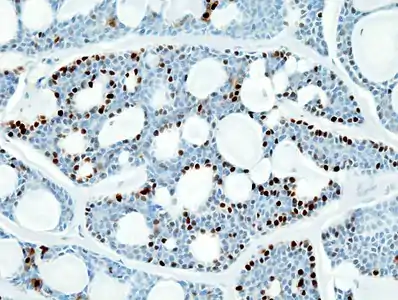

Histopathological image of adenoid cystic carcinoma of the salivary gland, immunostain for S-100 protein